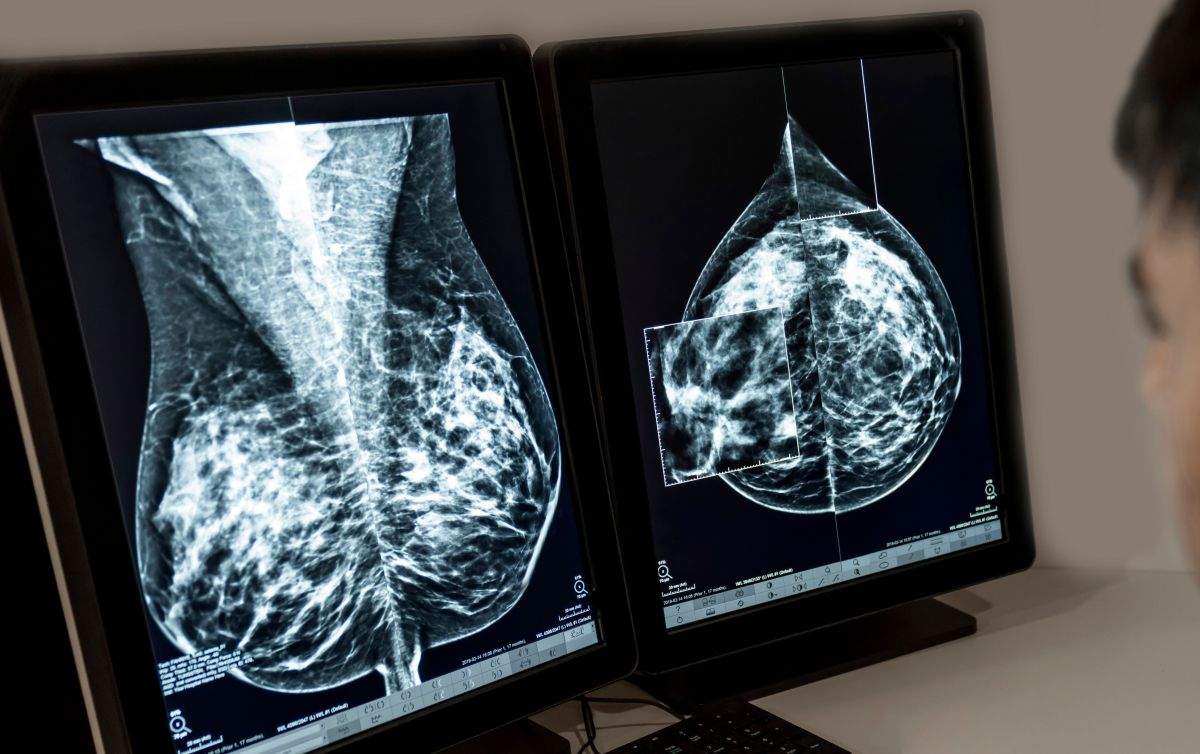

El càncer de mama és el càncer que es diagnostica amb més freqüència a Europa, i aproximadament el 70% dels casos, en etapes primerenques de la malaltia. Malgrat les opcions terapèutiques actuals, les persones diagnosticades amb càncer de mama localitzat HR+/HER2- en estadis II i III segueixen corrent el risc que el seu càncer reaparegui a llarg termini, sovint com una malaltia avançada incurable.

L'aprovació de ribociclib es basa en les dades de l'estudi de Fase III NATALEE, que va incloure una àmplia població de pacients amb càncer de mama localitzat HR+/HER2- en estadis II i III, incloent aquells sense afectació ganglionar amb elevat risc de recaiguda. L'estudi va mostrar una reducció significativa i clínicament rellevant del 25,1% en el risc de recaiguda de la malaltia amb aquest fàrmac ajudant en combinació amb teràpia endocrina (TE), en comparació amb TE en monoteràpia. El benefici de supervivència lliure de malaltia invasiva (SLEi) es va observar de forma consistent en tots els subgrups de pacients.